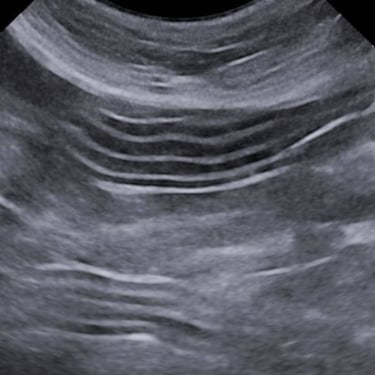

Practicing companion animal veterinary medicine in Simcoe County since 2012, Dr. Elyse is experienced in a variety of clinical settings from emergencies to chronic disease management and routine care.

Focusing on efficiency, workflow, and accuracy to provide actionable information to pet parents and veterinarians, while keeping patient wellbeing at the forefront.

Dr. Hauer has completed over 270 formal hours of continuing education in diagnostic abdominal and cardiac ultrasound from a variety of experts in the field, including a year-long immersive Advanced Imaging program through the Academy of Veterinary Imaging in Arlington, TX. She is a member of the International Veterinary Ultrasound Society.